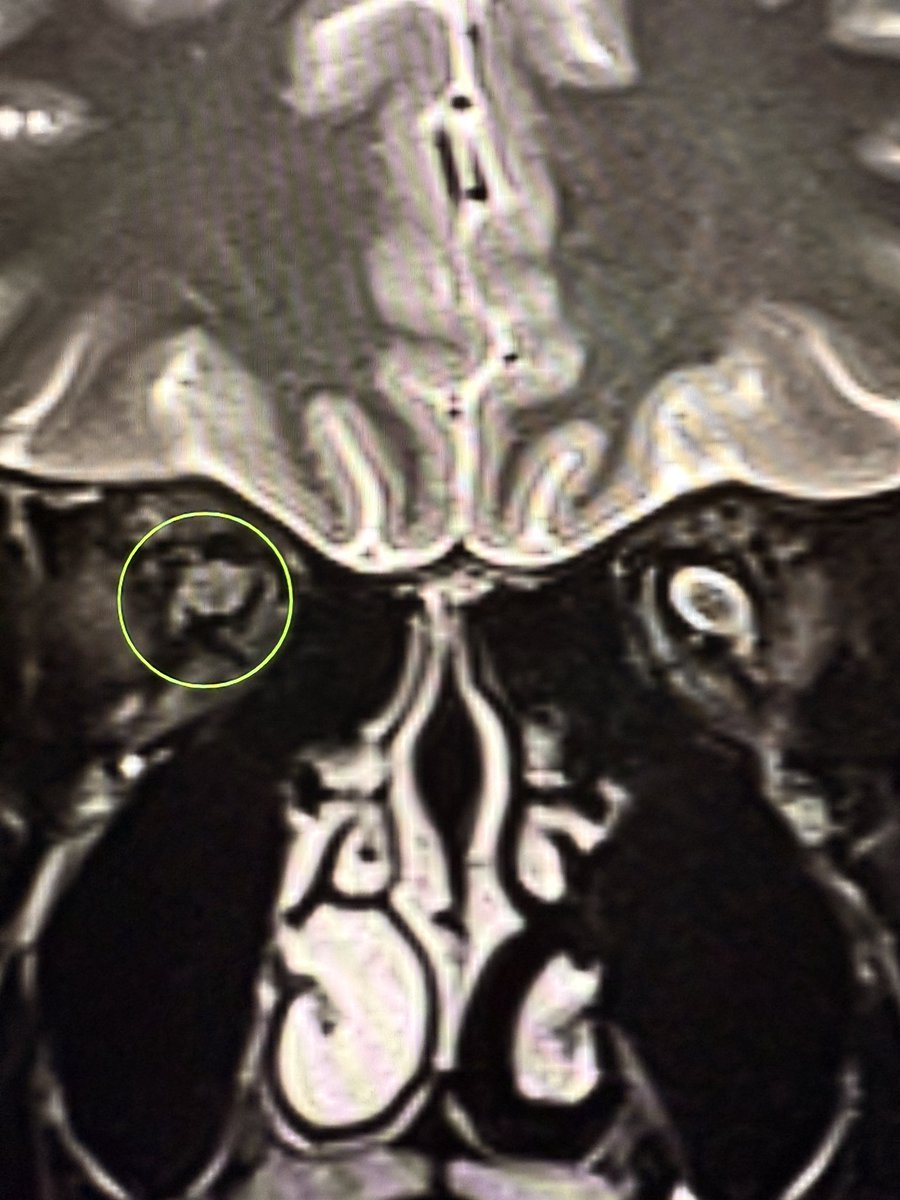

Optic nerves on T2 fat-sat coronal: Normal side → crisp bright CSF rim around the optic nerve. Optic neuritis side → swollen nerve, CSF cuff lost, rim disappears. A simple way to remember: when the halo vanishes, think neuritis. I call this the “Halo-loss sign” of optic

Optic nerves on  T2 fat-sat coronal:

Normal side → crisp bright CSF rim around the optic nerve.

Optic neuritis side → swollen nerve, CSF cuff lost, rim disappears.

A simple way to remember: when the halo vanishes, think neuritis.

I call this the “Halo-loss sign” of optic